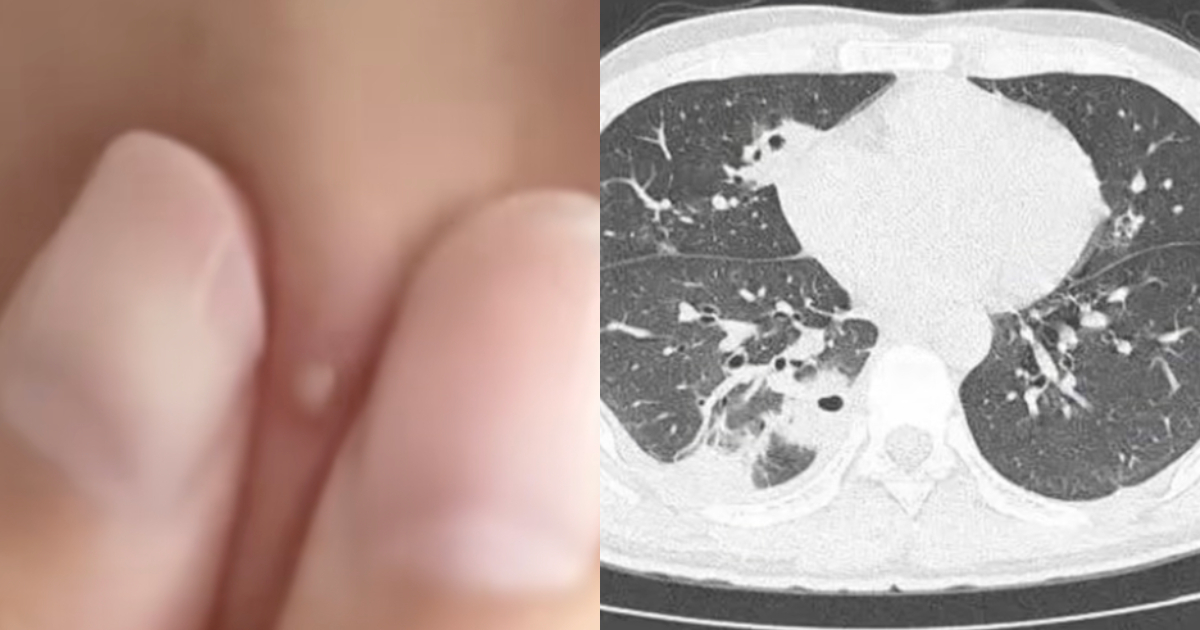

但幾天後,小林臉上的痘痘化膿,還出現發燒、咳嗽,呼吸困難的症狀,右下胸像針刺一樣疼痛,深呼吸時甚至會痛到冒冷汗。

醫生檢查發現,小林肺部有十多個空洞,而且部分肺組織壞死,是典型的「血源性肺膿腫」,這是一種因細菌感染導致肺部組織壞死並形成充滿膿液的空腔。

此外,小林的血液裡還檢測出金黃色葡萄球菌,這種細菌藏在每個人的皮膚表面。

而且,小林沒有洗手,擠痘痘時把細菌擠進血管,引發了敗血症,細菌侵蝕到肺部,引發炎症。所幸,小林年輕、身體素質好,經過12天的治療,最終康復出院。